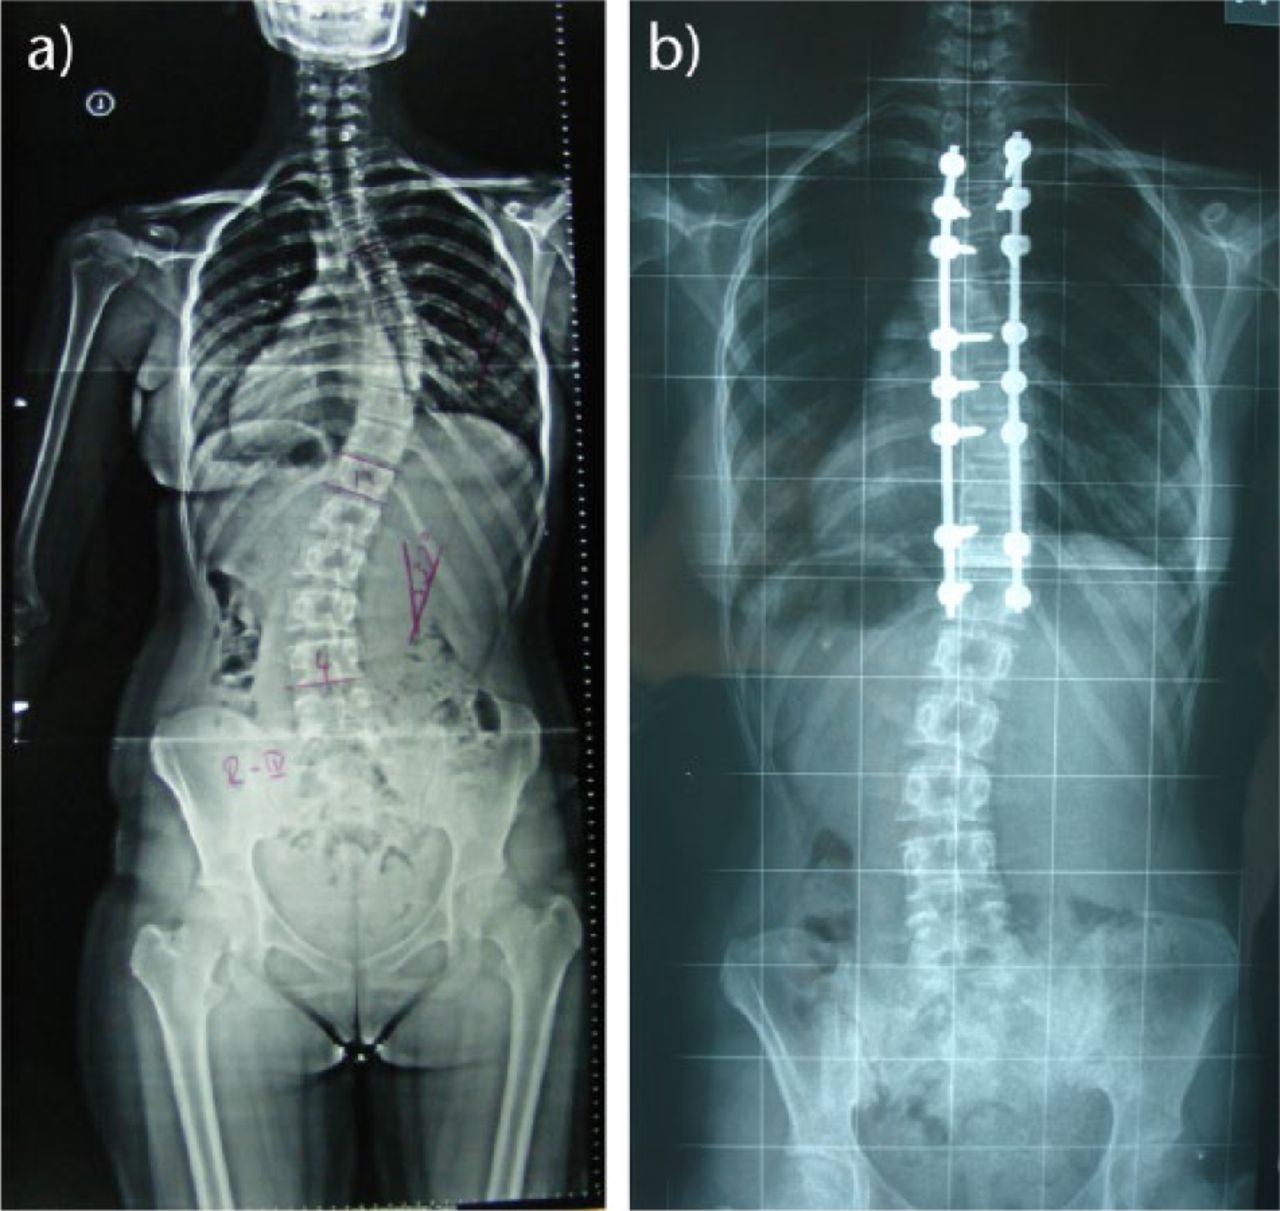

Before and After Scoliosis Surgery with Darryl Antonacci Spine Correction Near Me Contact our spine surgeon now. The affected area of the spine will be. He has also helped develop management pathways in the above procedures, reducing the hospital stay required after major spine surgeries. 15,112 likes · 15 talking about this · 252 were here. Complex thoracic and lumbar spine decompression and reconstruction for deformities, infection and spine tumour surgeries; Stand. Spine Correction Near Me.